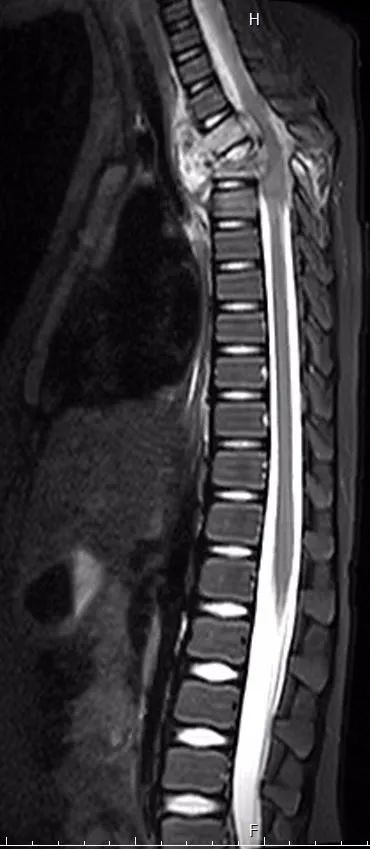

▶ 手术前,第2,3胸椎结核,大量死骨、脓液,脊柱后凸,压迫脊髓

6岁的小郭同学经历了一场劫难,去年春节前被救护车从江苏送到同济医院急诊室,在当地诊断胸椎结核,做了穿刺抽脓,病情却不见好转,1周之内双腿逐渐瘫痪。病儿父亲和奶奶通过病友的推荐,慕名找到同济医院脊柱外科。收住病房时,病儿双下肢感觉运动已完全丧失,大小便失禁;人很瘦弱,发着低烧,病痛加上陌生的环境,不停地哭闹。治疗组迅速完善检查,同时协调上海市肺科医院会诊给出儿童的抗结核药物治疗方案。磁共振、CT检查的结果显示第2,3胸椎骨质被结核菌侵蚀得千疮百孔,而且已经塌陷后凸,周围大量的脓液包裹着胸主动脉和脊髓,因而造成了病儿下肢瘫痪;而且病儿血沉很高、营养差、肝功能也不好。面对病情重、年龄小、体质差、时间紧一堆困难,脊柱外科迎难而上,果断决定尽早手术,清除死骨和脓液,矫正后凸畸形,挽救神经功能,否则病儿余生要在轮椅上生活了。科室组织全院会诊,儿科、感染科保障围手术期的用药,麻醉科、ICU、输血科保障手术的安全,医学影像科、胸心外科建言主动脉和胸膜的保护,护理组、康复组保障手术后的护理康复,群策群力为特殊的小病人付出最大关爱。

▶ 手术后11个月,胸椎结核治愈,后凸矫正,植骨融合